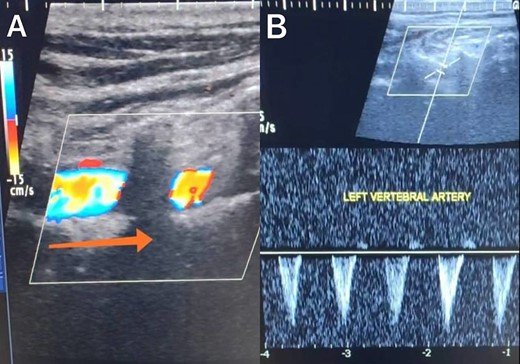

A 65-year-old male presented with recurrent transient ischemic attacks (TIAs), characterized by severe balance disturbances, transient alterations in consciousness, and visual obscurations. Clinical examination revealed high blood pressure in the right arm and absent left radial and brachial artery pulses. Vital signs were normal. Laboratory tests are analyzed as follows: urea: 22 mg/dl, glucose: 150 mg/dl, cholesterol: 199 mg/dl, and triglycerides: 222 mg/dl. A medical history of type 2 diabetes mellitus (DT2), hypertension (HTN), hyperlipidemia, ischemic heart disease, and a heavy smoking history were recorded. Five years before presentation, the patient underwent coronary stenting. Medication history included metformin 1000 mg, aspirin 81 mg, rosuvastatin 40 mg, and ramipril 5 mg. Neck duplex ultrasound (DU) showed normal flow direction and insignificant atherosclerotic plaques in the left internal carotid artery (CA) and left external CA (Figs 1 and 2), normal common CA (Fig. 3), a completely inverted flow direction in the left VA (Fig. 4) that suspected a significant ostial lesion in the left SCA. Multi-slice computed tomography angiography demonstrated 99% stenosis at the left SCA origin and confirmed the presence of SSS (Fig. 5). A balloon angioplasty was unsuccessfully attempted to expand the left SCA. A left carotid VA bypass surgery was performed, and a vascular graft was used to establish a blood flow pathway between the left VA and the left CA. By follow-up, the patient was stable without complications.

Duplex ultrasound showing a completely inverted flow direction in the left vertebral artery.

With a prevalence ranging from 0.6% to 6.4%, SSS is considered a rare phenomenon, and high suspicion is required for diagnosis [2, 5]. The basilar artery is formed by the two vertebral arteries and connects to the brain’s anterior circulation, comprising the Willis circle. However, a steno-occlusive lesion of the proximal SCA may lead to limited blood flow to the upper extremity. Consequently, blood flows through the contralateral VA to the basilar artery, around the circle of Willis, and then descends through the IVA to supply the affected upper extremity, leading to upper limb and vertebrobasilar insufficiency. This altered physiology manifests in signs and symptoms constellation defining SSS [1, 4]. A total of 82.3% of lesions primarily affect the left side as a result of the sharper curvature at the origin of the left SCA, which increases blood flow turbulence and promotes atherosclerotic plaque formation [1, 2, 5–7]. In this case, a patient with retrograde left VA flow on DU is presented (Fig. 4). Most patients are asymptomatic due to developing collateral circulation [2]. However, it may manifest with arterial insufficiency affecting the upper limb (paresthesia, weakness, and claudication), the brain (vertigo, dizziness, diplopia, ataxia, dysarthria, slurred speech, and syncopal episodes) [1, 2, 5, 7], or the heart if the patient has a coronary artery bypass graft supplied by the internal mammary artery [6]. Our patient suffered from recurrent TIA, manifested as severe balance disturbances, transient altered mental status, and amaurosis fugax (transient vision loss). The most common diagnostic tests for SSS are the DU and TDU due to their accessibility and low cost, which show the subsequent retrograde blood flow in the IVA. Additionally, MRA or CT angiography is used as a confirmatory modality [1, 2, 5–8], but the gold-standard is conventional cerebral angiography [1]. A difference in blood pressure readings between arms >20 mmHg is a significant and noticeable sign. In our case, neck DU showed an inverted left VA flow direction (opposite to the carotid) (Fig. 1). MSCT confirmed the diagnosis of SSS, demonstrating a significant ostial lesion in the left SCA. Conservative management is preferred with minimally symptomatic patients by reducing risk factors like a specific regime and treating comorbidities such as: HTN, DT2, hyperlipidemia, and smoking cessation as a part of minimizing morbidity and preventing complications [1, 2, 5–8]. Surgery is recommended for severe and untreated cases through percutaneous intervention or surgical revascularization by using vascular bypass accompanied by angioplasty and stenting [1, 2, 5–7]. In our case, expanding the left subclavian by catheterization did not succeed; however, a left carotid-vertebral bypass was successfully performed. The most common complications are stroke (ranging from 0.4% to 4.7%) due to distal emboli, thrombosis or bleeding and rupture because of aggressive catheter or wire manipulation [1, 7]. In our case, the patient continues on HTN and DT2 medications: ramipril 5 mg, rosuvastatin 40 mg, aspirin 81 mg, and metformin 1000 mg.